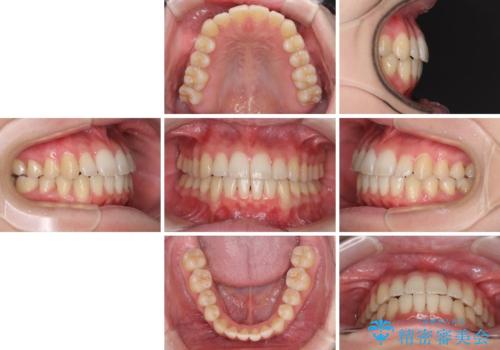

- ちょっとしたデコボコを整えたいとのことで来院された患者様です。

歯列不正は軽微であったため、インビザライン・ライトにより、費用を抑えて矯正治療を行うこととしました。

上下前歯の捻れが改善され、患者様には大変満足していただきました。